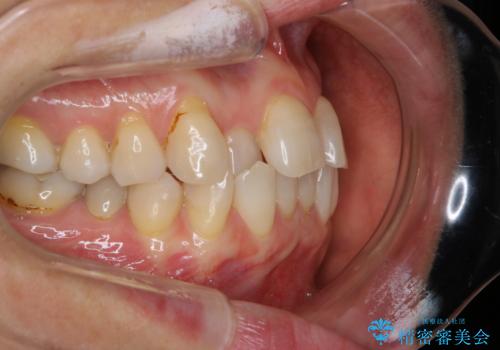

前歯の反対咬合、奥に引っ込んでしまっている歯をインビザラインで治療する

- インビザラインでの治療を希望した患者様です。

上の前歯の反対咬合があり、治療の途中で下の前歯を乗り越える必要があります。

インビザラインでこのような症例を行う場合、乗り越えるのに必要な期間が長くなります。

その為、奥歯で咬みにくい期間が長くなってしまいやすいです。